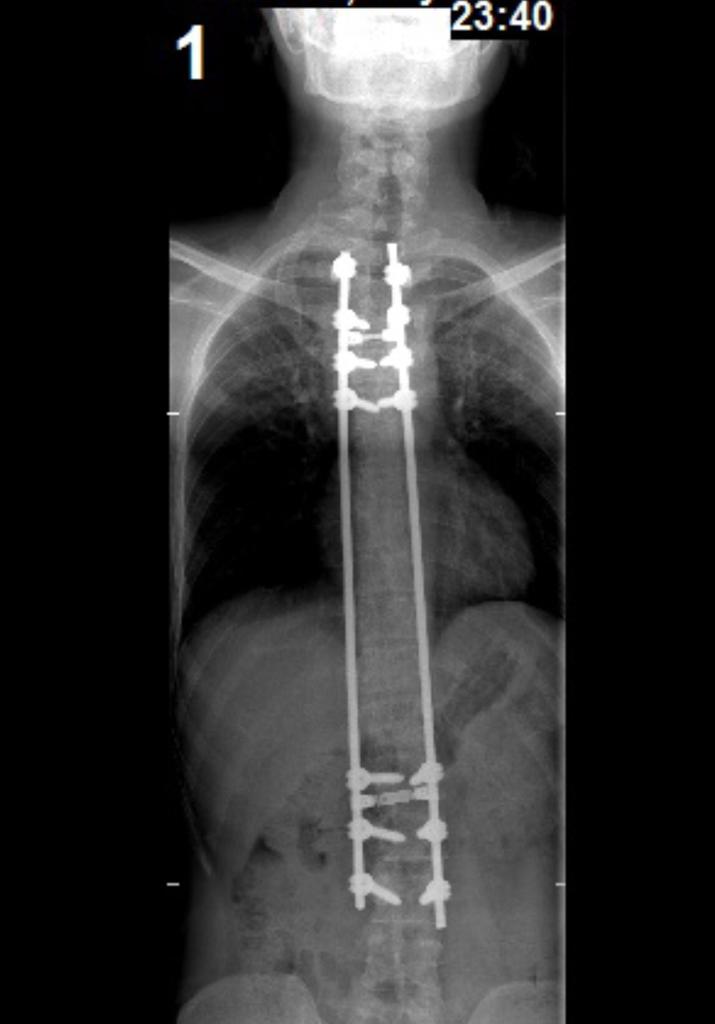

أي أحد تعرفه يفكر يسوي هالعمليه

علمه ان ظهره بينفتح مثل الذبيحه

وان العمليه تجر عمليات

وعمره ما راح يرتاح

أي واحد بيسوي العمليه لازم يفهم إن مهما قالوله الأطباء وسهلوها له مافي إنسان يتحمل يتكسر عموده الفقري وتنغرز هالبراغي بفقراته وتنشد بأصياخ

لم تنجح العمليه

هالشي حصل مني ونبهني البعض إني أدخلت الرعب في قلوب الكثير من إجراء عمليه تصحيح العمود الفقري .

لذلك أنبه ان إلي صار معي يعتبر حالة شاذه والكثير سوو العمليه ونجحت وعايشين حياتهم بشكل طبيعي .